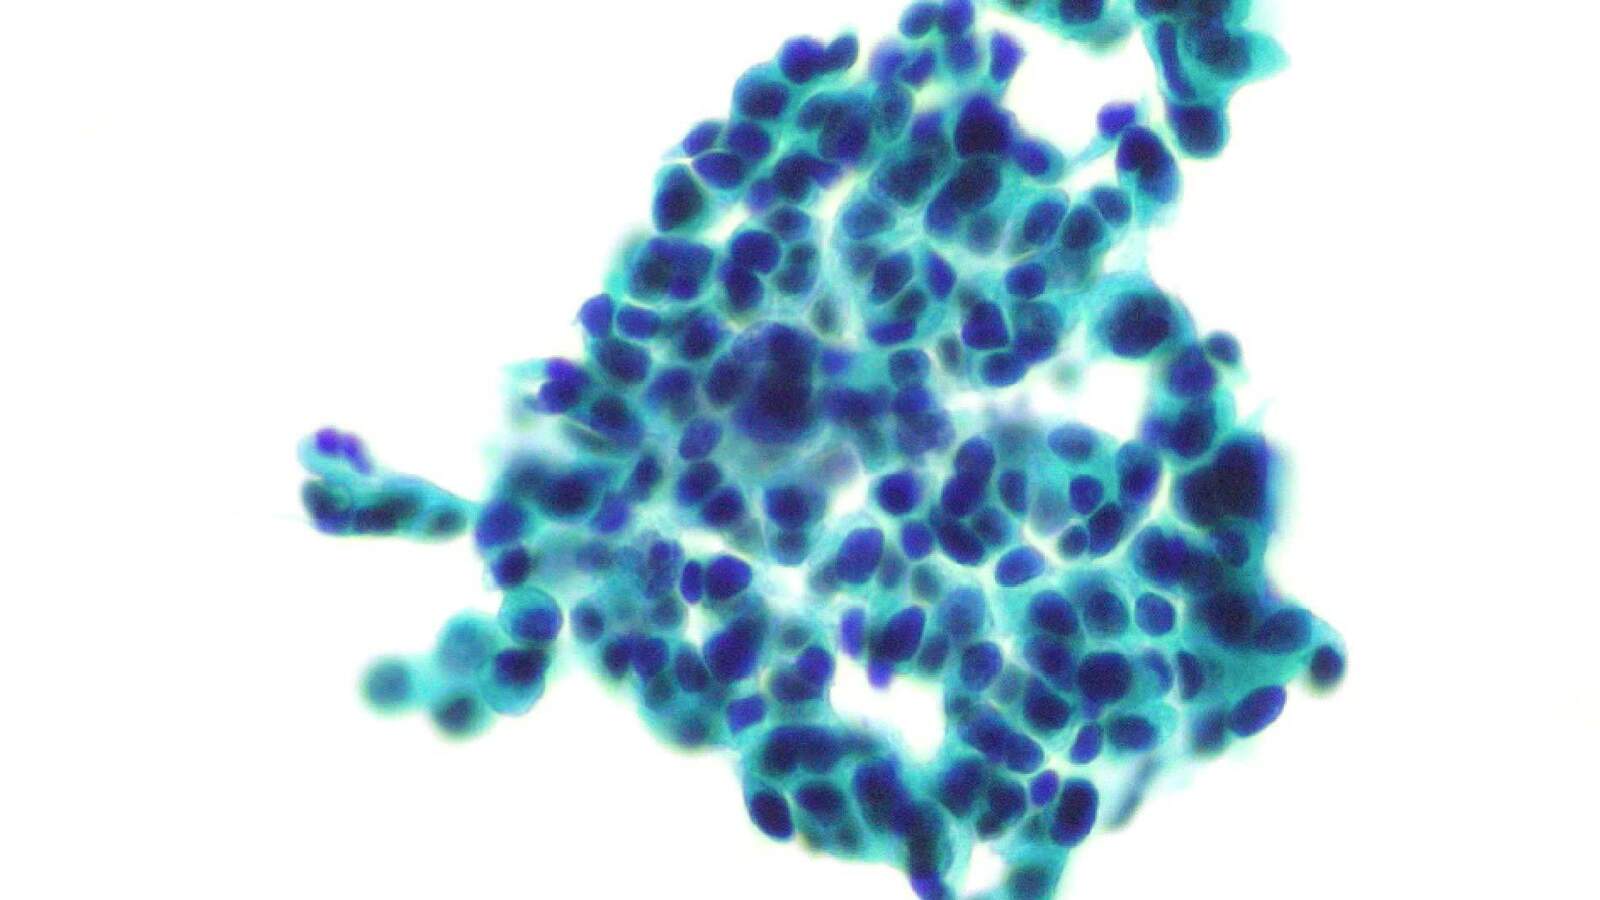

明场观察(Bright field),是显微镜技术中最基础且应用广泛的观察手段之一。这种方法利用均匀分布的光线直接照射在样本上,使观察者能够清晰地看到样本中吸收或散射光线的部分,从而获取其形貌和结构信息。

明场观察方式在多个学科领域都发挥着不可或缺的作用。在生物学领域,它常被用于研究细胞、组织、细菌等生物样本的微观结构和功能。在医学领域,明场观察则是病理学检查、临床实验室检测和血液分析等工作的重要辅助手段,为医生提供了宝贵的诊断依据。此外,在材料科学、环境科学等领域,明场观察同样发挥着重要作用,有助于研究人员深入了解材料的微观结构和性质。

应用领域:常规镜检、病理、染色标本